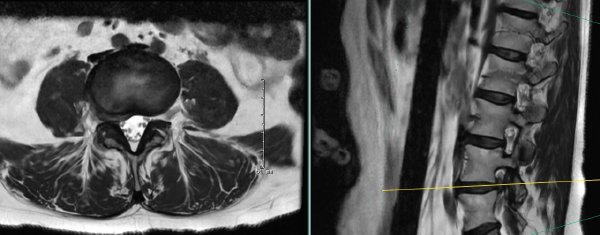

Preoperative MRI showing far lateral and foraminal right L4-5 disc herniation

Her imaging demonstrated a sizable paracentral and far lateral disc herniation on the right side at L4-5. She had obtained an initial opinion at a neighboring tertiary care academic medical center who recommended a fusion as they felt that a total facetectomy was needed to fully decompress the existing and traversing nerve root.